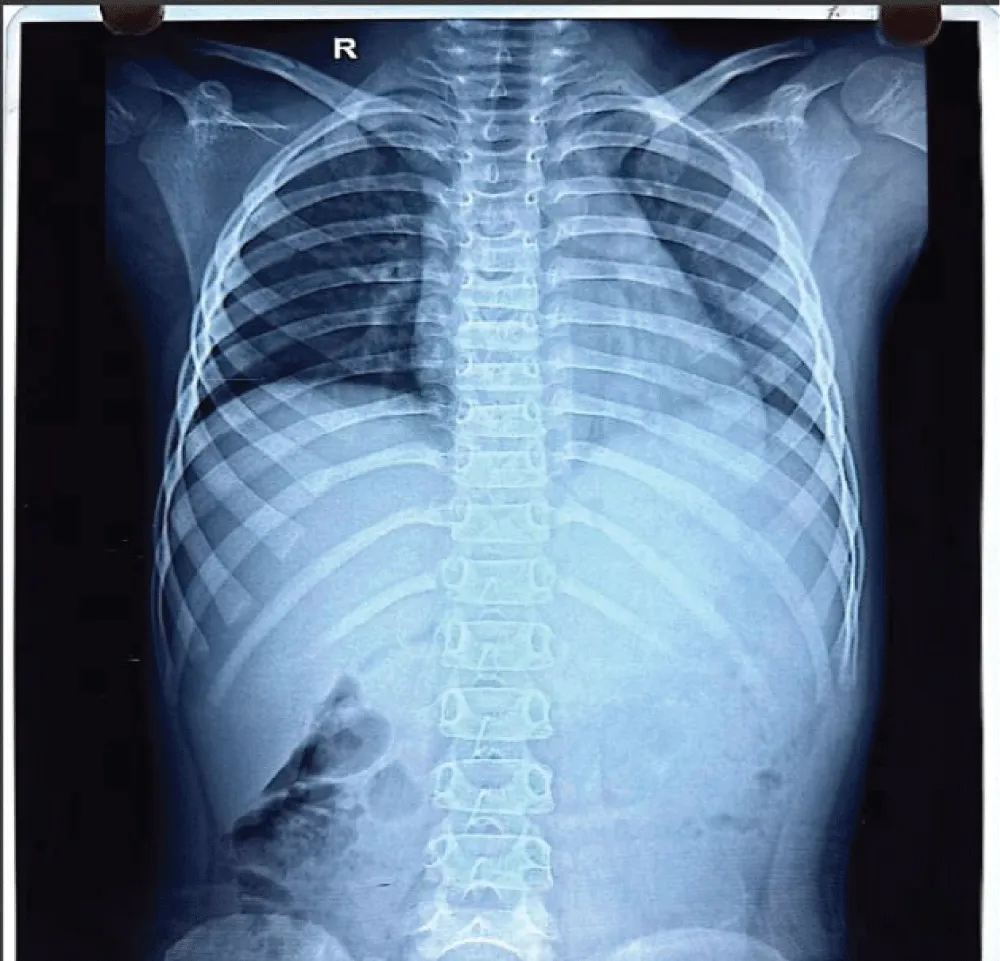

A mother with 6 year old female child presented to our Orthopedic Out Patient Department. She had not been able to move her right elbow in full range with restricted active and passive movements and appeared distressed. According to the informant (mother), she had been apparently well 2 months back when she was hit by rear wheels of a tractor while playing on the roadside. She developed pain and swelling in the elbow and was immediately rushed to the nearby hospital. Routine investigations, CT scan of abdomen and pelvis and X-ray of right elbow and hand were done. (Figures 1-3). All reports were normal except X-ray arm diagnosing undisplaced low lying supracondylar fracture of the right humerus (Figure 3). The child was admitted to the hospital and right upper limb was immobilized in an above-elbow plaster slab, with the elbow in 90o flexion (Figure 4). She was discharged after 4 days with reportedly normal radiographic findings.

Laboratory test results at presentation showed a white blood cell count of 7,900/µL and the C-reactive protein was negative ruling out infectious or inflammatory component. Additionally, urine analysis was unremarkable, showing no evidence of proteinuria, hematuria, or infection, further supporting the localized nature of the condition.